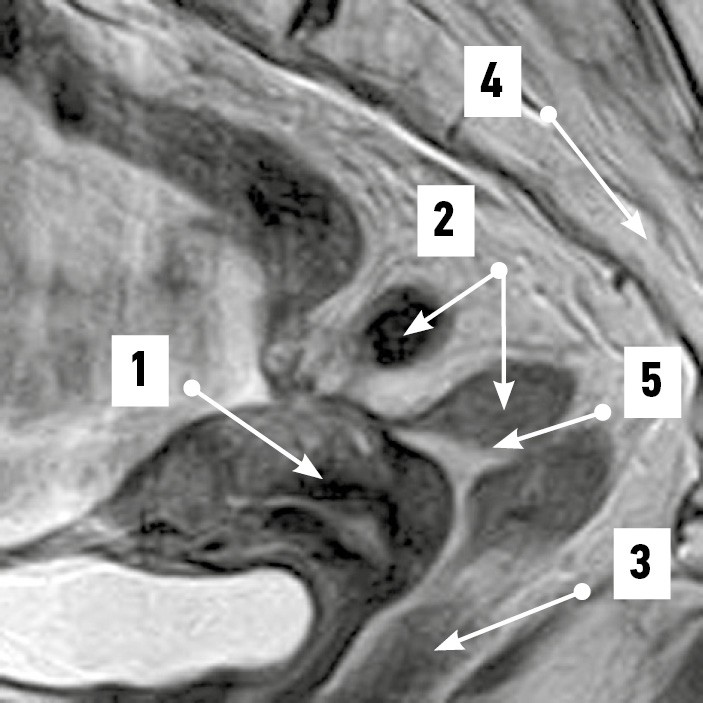

При положениях dextrodeviatio uteri на уровне надвлагалищного участка прямой кишки в 75% случаев крестцовый изгиб кишки в сагиттальной плоскости сочетался с изгибами во фронтальной плоскости (рис. 7). Ещё в 25% случаев определялся сагиттальный изгиб, соответствующий тазовой поверхности крестца. Среднее расстояние от матки до прямой кишки в надвлагалищном участке соответствовало 5,56±0,66 мм. Разброс величин составил 2,97–11,4 мм.

Рис. 7. Извитой во фронтальной плоскости надвлагалищный участок прямой кишки. Магнитно-резонансная томограмма органов таза в режиме SG T2: 1 — матка; 2 — надвлагалищный участок прямой кишки (извит во фронтальной плоскости); 3 — влагалищный участок прямой кишки. / Fig. 7. Supravaginal portion of the rectum convoluted in the frontal plane. SG T2-magnetic resonance imaging of the pelvic organs: 1 — uterus; 2 — supravaginal segment of the rectum (convoluted in the frontal plane); 3 — vaginal segment of the rectum.

Во влагалищном участке в 91,67% случаев визуализировался крестцовый изгиб кишки, и лишь в 8,33% он сочетался с изгибом во фронтальной плоскости. Среднее расстояние между органами во влагалищном участке составило 1,47±0,27 мм.